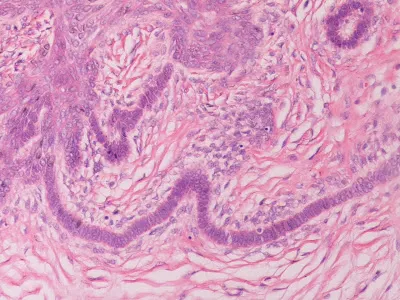

Genel Patoloji (Ders Notları)